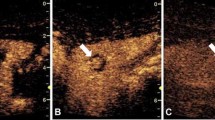

The current primary application of 3-D/4-D CEUS in children is an effort to augment the diagnostic accuracy of 2-D contrast-enhanced voiding urosonography (VUS). Recent studies showed that the sensitivity of 3-D/4-D contrast-enhanced VUS in vesicoureteral reflux (VUR) detection is comparable to standard 2-D contrast-enhanced VUS [21]. Some studies suggest that 2-D and 3-D/4-D contrast-enhanced VUS detect more reflux than does fluoroscopic voiding cystourethrography (VCUG), but 3-D/4-D techniques might provide additional information and improve the grading accuracy of VUR compared to 2-D contrast-enhanced VUS alone, which can have important clinical implications [21,22,23]. Specifically, 3-D/4-D contrast-enhanced VUS with advanced post-processing options (e.g., rendering, sharpening, contrasting, zooming, rotating the image) as well as artifact removal, can improve depiction of the pelvicalyceal system and ureter by showing visible borders distinct from the surrounding structures, thus offering more detailed morphological visualization of the reflux (Fig. 1) [21, 22]. Such a precise visualization of the collecting system might be of value in children with abnormal renal rotation or position. Another considerable advantage of the 3-D/4-D technique is the capability to document reflux in a manner analogous to fluoroscopic VCUG, e.g., in the anatomical directions of the kidneys. This approach seems to be more comprehensive when interacting with the referring physicians [21,22,23]. Recently, the 3-D/4-D technique has also been applied during the micturition part of the contrast-enhanced VUS examination for improving visualization of urethral abnormalities in both female and male patients [22].

Three- and four-dimensional contrast-enhanced voiding urosonography (VUS). a Sagittal contrast-enhanced VUS in a 7-month-old boy with dual display of two-dimensional (2-D) images of the right kidney in gray-scale (left) and contrast (right) modes demonstrates US contrast agent filling the right renal collecting system (arrow). b, c Three-dimensional (3-D)-rendered contrast-enhanced VUS images of the right kidney in anterior projection (b) and posterior projection (c) demonstrate contrast opacification of the right renal collecting system including the pelvis (arrows), calyces (asterisks) and ureter (arrowheads) to better advantage than 2-D contrast-enhanced VUS static images; the latter images also demonstrate multiple angles, with improved visualization of the calyceal dilation, possibly allowing for more accurate grading of the vesicoureteral reflux